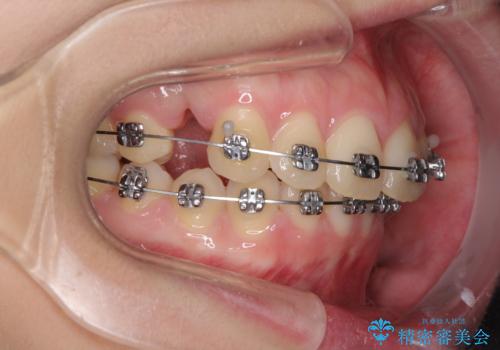

- メタルブラケット

- 3年1ヶ月

- 10-30回

左右ともに上顎奥歯が外を向き、下顎奥歯が内側に倒れているシザーズバイトであったため、補助装置により改善することとしました。

上下の咬み合わせは、下顎に対して上顎が相対的に前方にあったため、奥歯のシザーズバイト改善後に上顎左右第一小臼歯2本を抜歯し、上顎前突を改善していくこととしました。